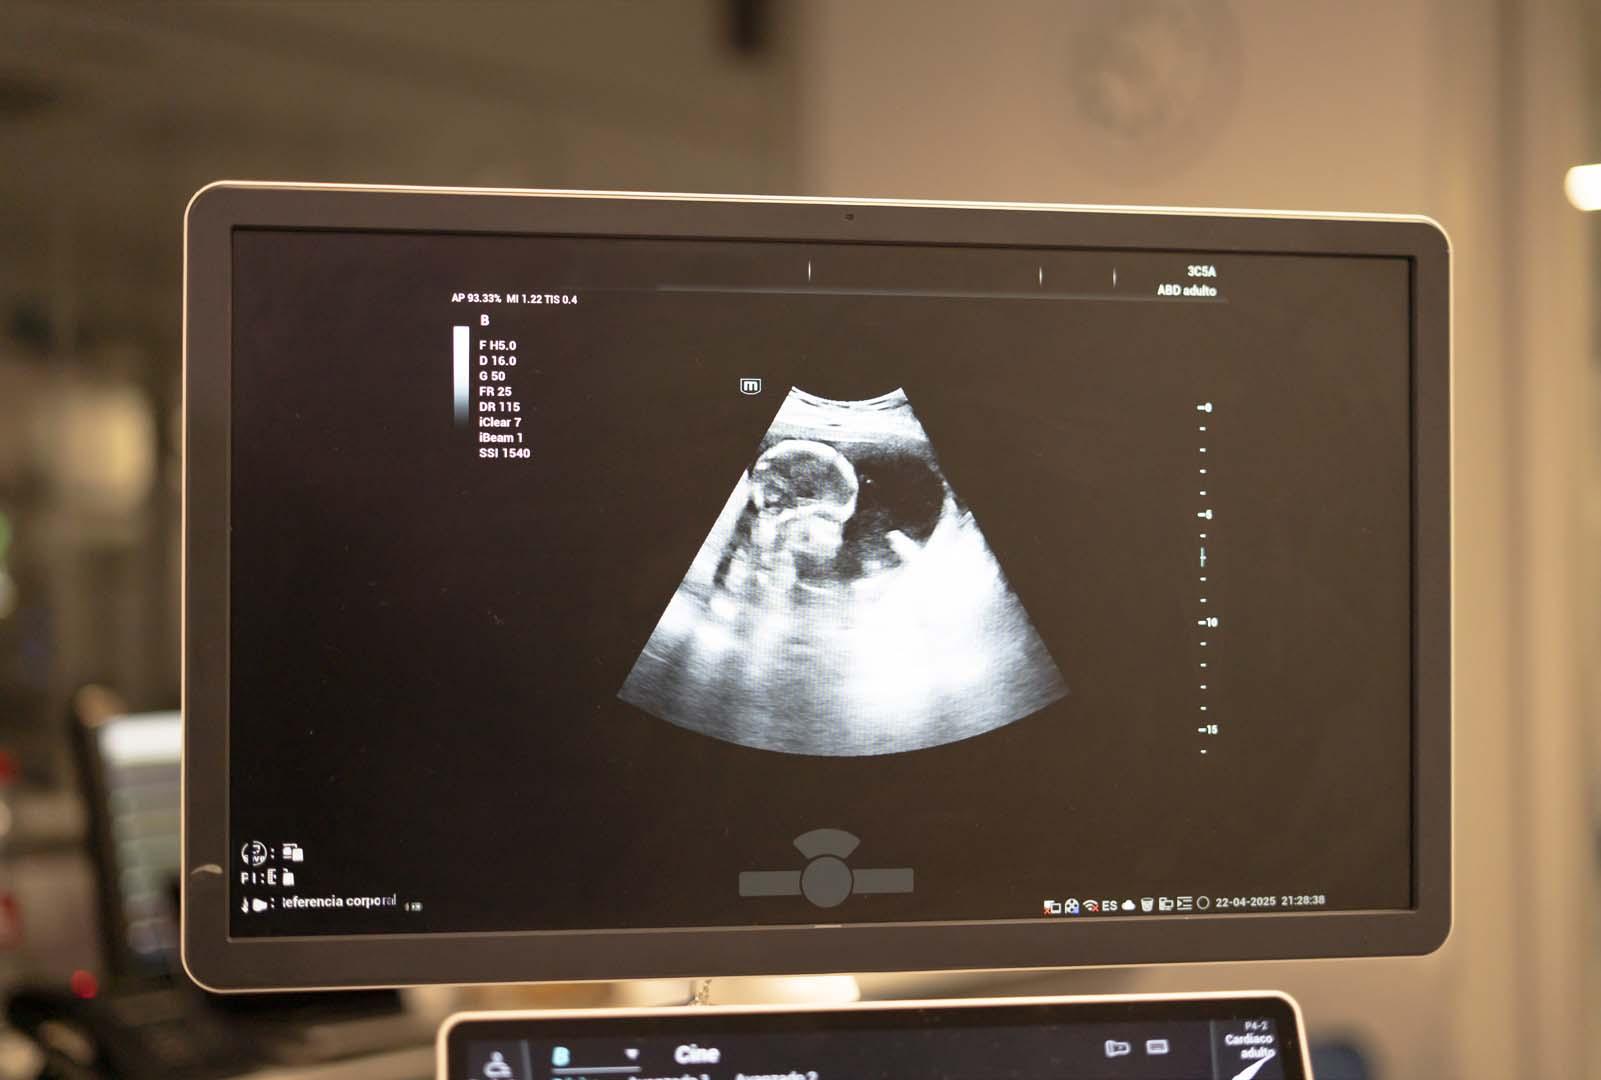

Hamileliğin ikinci döneminden başlayarak geleceğin anneleri, bebeklerinin tekme atışlarını, vücut dönüşlerini ve hatta hıçkırık seslerini hissedebilmektedir. Peki bu dönemde fetüsün başka hangi hareketleri yapabileceği sorusu merak konusu olmuştur. Bilim insanları, ultrason görüntüleri sayesinde anne karnındaki bebeklerin ağlamaya benzer mimik hareketleri gerçekleştirdiğini gözlemlemişlerdir.

Modern ultrason teknolojileri, embriyoların gelişim sürecini detaylı bir şekilde gözlemlenmesini mümkün kılmıştır. Bu ileri teknoloji sayesinde araştırmacılar, fetüsün çeşitli hareketlerini ve mimiklerini kayıt altına alabilmektedir. Archives of Disease in Childhood — Fetal and Neonatal Edition adlı tıbbi yayında yayınlanan video kayıtlarında, 33 haftalık bir embriyonun ağlamaya oldukça benzer yüz ifadeleri sergilediği açıkça görülmektedir. Bu bulgular, fetüsün anne karnında sadece pasif bir şekilde gelişmediğini, aksine aktif hareketler yaptığını göstermektedir. Ultrason teknolojisinin bu kadar ileri seviyelere ulaşması, tıp alanında yeni kapılar açmış ve fetüsün davranışları hakkında daha fazla bilgi edinilmesini sağlamıştır.